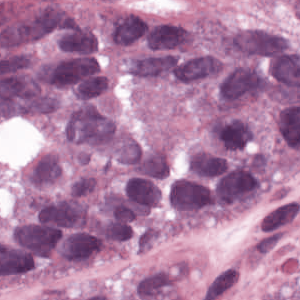

As an essential part of digital pathology, histopathology image analysis is playing increasingly important role in cancer diagnosis, which can provide direct and reliable evidence to diagnose the grade and type of cancer. This paper deals with nuclei segmentation, an important step in histopathological image analysis. The purpose of nuclei semgentation is not only counting the number of nuclei but also obtaining the detailed information of each nucleus. So unlike nuclei detection, here the outputs are the contour of each nucleus instead of only the position of their central points. Hence we can exactly extract each nucleus from the image and make it available for further analysis. For example, the features of the individual nucleus and the distribution of nuclei clusters can be used to grade and classify status of breast cancers [3, 4]. Because of appearance variation such as color, shape, and texture, nuclei segmentation from histopathological images could be very challenging, as illustrated in Fig.1, in which it is very challenging even for human to recognize and segment all nuclei within the images. Fig.1(a) and Fig.1(b) illustrate two histopathological images from different organs. Fig.1(c) and Fig.1(d) are two histopathological images from same organ but have different cancer grade.

H&E stain is the most widely used stain protocol in medical diagnosis. Typically, the nuclei of cells are stained to blue by Haematoxylin while cytoplasm is colored to pink by Eosin. But in practice, the color of H&E stained images could vary a lot due to variation in the H&E reagents, staining process, scanner and the specialist who performs the staining, as shown in Fig.1. A few H&E stain normalization methods[23, 24, 25] have been proposed to eliminate the negative interference caused by color variation. We tried two of them[23, 25] to normalize the raw H&E stained images. For our segmentation algorithm, we did not find any considerable difference between these two normalization methods. Particularly, the result shown in experiment section III is generated based on the images normalized by the method in [23]. Given a target image, this method is able to convert one image’s color into the target image’s color space based on sparse non-negative matrix factorization(NMF). We choose one best stained H&E image as the target and convert other images into its color space. According to the recommendation in [23], the hyper-parameter should be set between 0.01 and 0.1. In our experiment, is set to 0.1.